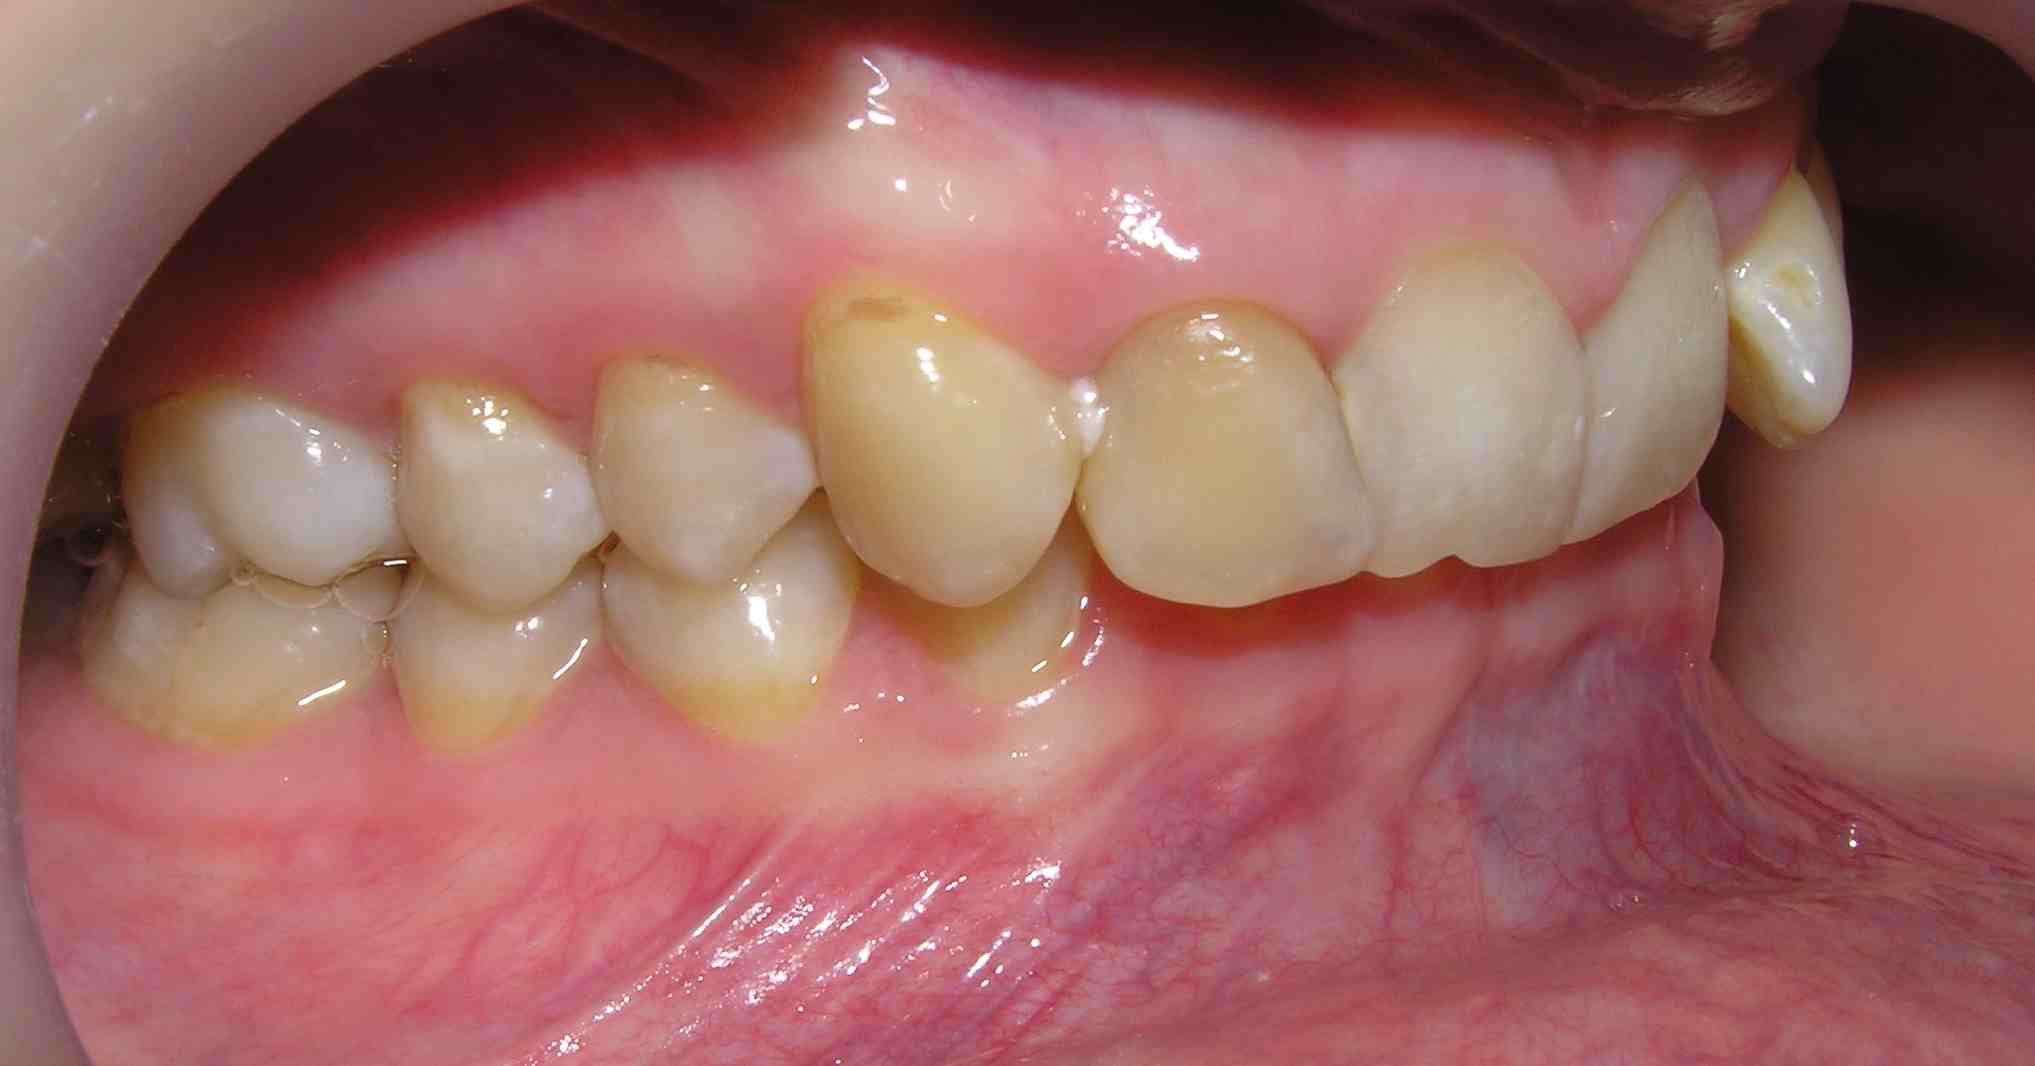

Pic.16. Mesial position of tooth 11 with lack of space in the dental arch.